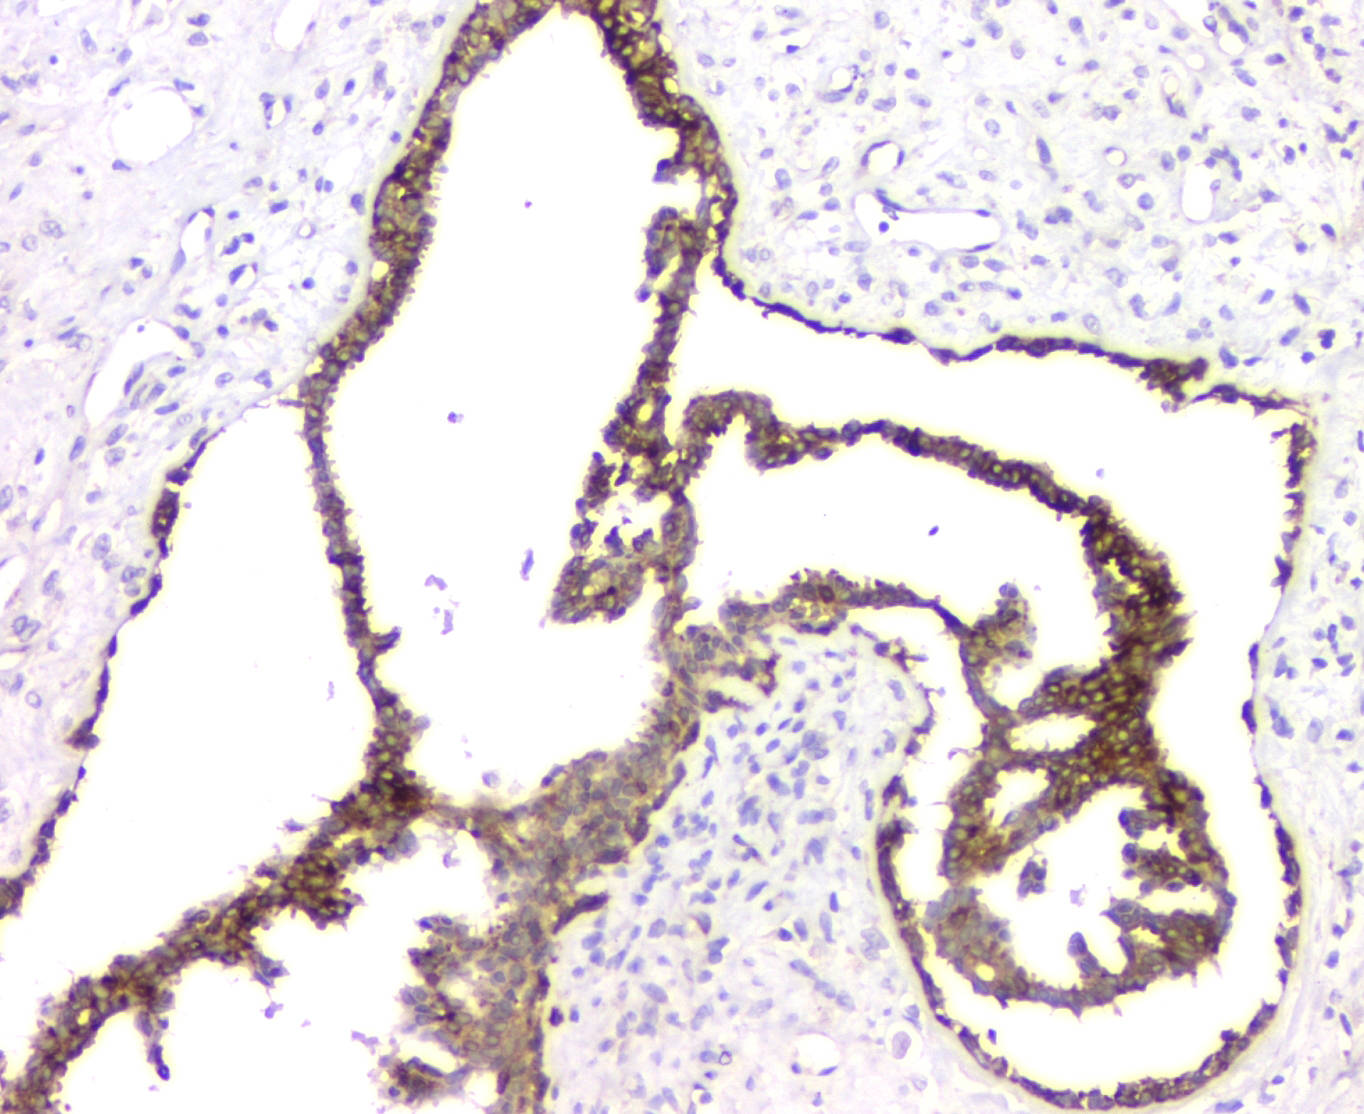

IHC analysis of RMI2 using anti-RMI2 antibody (A08685).

RMI2 was detected in a paraffin-embedded section of human mammary cancer tissue. Biotinylated goat anti-rabbit IgG was used as secondary antibody. The tissue section was incubated with rabbit anti-RMI2 Antibody (A08685) at a dilution of 1:200 and developed using Strepavidin-Biotin-Complex (SABC) (Catalog # SA1022) with DAB (Catalog # AR1027) as the chromogen.